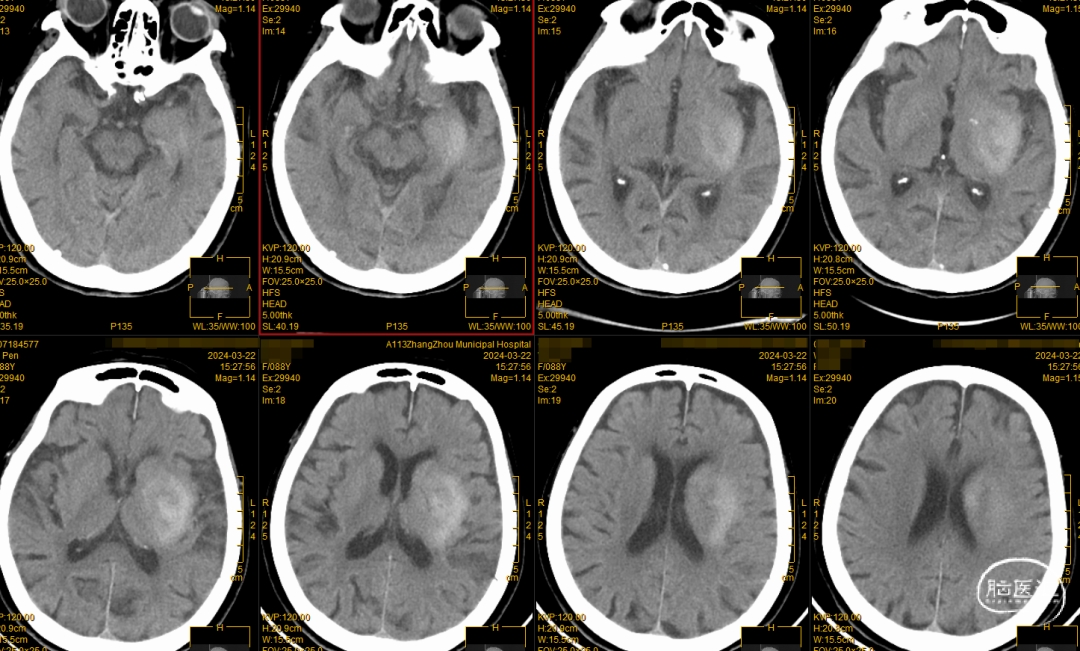

颅脑CT平扫

CTA